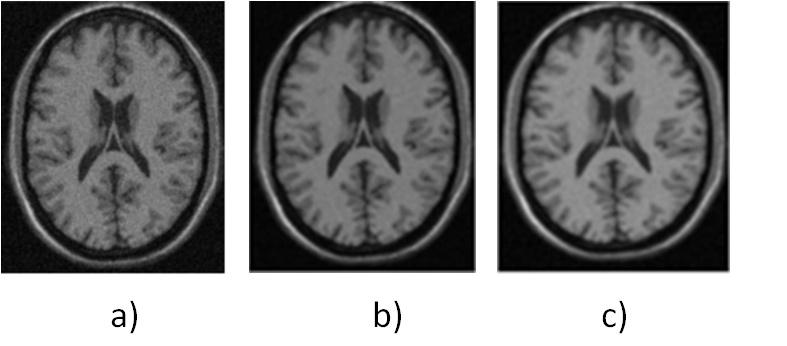

Figure 1 presents axial views of the information contained in selected images of the BrainWeb database.

The selected volume of the BrainWeb base contaminated with Rician noise was filtered, independently, using both the techniques of anisotropic and Gaussian filtering. Because this volume is heavily contaminated, it is possible to visualize easily the Rician noise in any of the axial, coronal or sagittal cuts.

For this reason, only one of them was chosen to present the information related to this type of noise. Thus, figure 2 allows the comparison of the axial view of the polluted volume with the smoothed versions, generated by each of the said filters.

A visual analysis of these images shows that both the anisotropic filter and the Gaussian smoothing manage to restore, to a large extent, the contaminated image. However, the qualitative analysis of these figures does not allow to establish, without ambiguity, which of the filters exhibits the best behavior; therefore, quantitative results obtained from the calculation of the PSNR are presented which will indicate, precisely, which of the filters delivers the best performance.